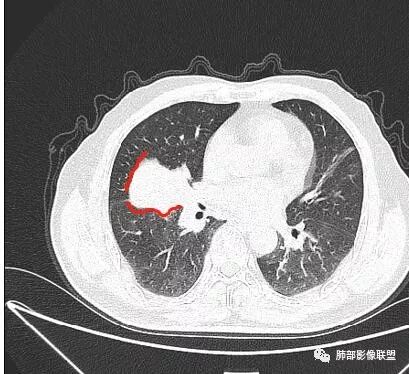

老年男性,亚急性病程,咳嗽咳痰。右肺中叶团片影,外朝内分布,大部分边界清楚平直,内侧支气管进入,团片影见低密度坏死区,强化明显,延迟强化,血管破坏不明显,符合爬行征5个特点:

1.肺外周生长。

2.外侧部分体积大于内侧。

3.病变最大径与肺的纵轴及水平面任何一条轴线不平行。

4.病变内侧支气管通畅。

5.病变区域肺容积无缩小。

双侧肺门及纵隔淋巴肿大并可见钙化。考虑结核,但部分边缘膨隆,肿瘤待排。

叶间裂推移方向

我们现在看主病灶,病灶紧贴叶裂:

我想看冠状位,就是看它长轴、病灶的整体形态

外围大、内带小

吴婧老师和南边老师都对该病例进行了深入分析。从支气管管壁的增厚,支气管狭窄后扩张,支气管粘液栓,病灶形态,到病灶不均匀强化及坏死彻底,到周边病灶及肺组织空气的潴留,加之纵隔内淋巴结肿大伴钙化等等,都支持慢性炎性病灶,尤其是结核。

现在小编来增加一个炎性另一个征象,是我们王兆宇老师原创的----就是墨西哥仙人掌征。

墨西哥仙人掌征---结核        影像上结核灶,粗大的均匀枝干,推测是支气管囊状扩张引起的,在非支气管区,形成圆形坏死囊群;如果这些坏死比较稀薄,又遇到扩张支气管,就会形成粗大的“墨西哥仙人掌”。结核引起的支气管近端炎症纤维化,可以造成支气管阻塞,从而将干酪样坏死物封堵在管腔内。仙人掌主干内部应该是干酪为主,稀薄的,具有流动性,时间久了会出现钙化。